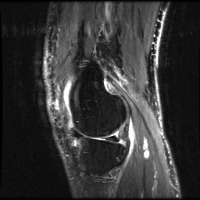

meniscal Computer Vision Project

Medical Diagnostics: Radiologists, orthopedic surgeons, and other medical professionals can utilize the "meniscal" model to accurately identify and classify meniscal lesions in knee MRI scans, thus improving the diagnosis and treatment process for patients with knee-related injuries and conditions.

Sports Injury Prevention and Management: Sports rehabilitation centers and athletic trainers can employ the "meniscal" model for analyzing knee scans of athletes to assess the health of their knees, track any changes over time, and tailor training regimens or treatments to prevent or recover from meniscal injuries.

Pre- and Post-Surgery Evaluation: Surgeons can use the "meniscal" model to analyze the knee scans taken before and after meniscal surgeries to evaluate the efficacy of the surgical intervention and make informed decisions about the patient's further treatment plan and rehabilitation process.